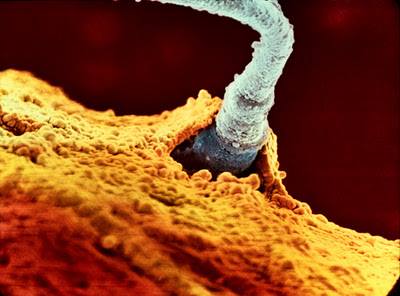

Սպերմատոզոիդն արգանդափողում

Ֆալոպյան փողը, որի միջով բեղմնավորված ձվաբջիջն անցնում է դեպի արգանդ: